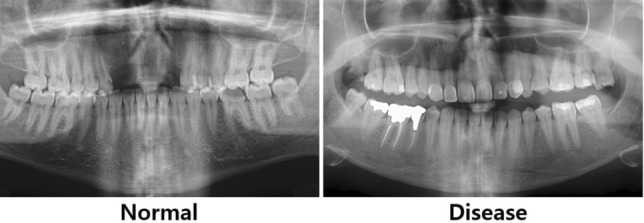

The second dataset consists of 256 photos in HUSHDD (Hanyang University Seoul Hospital Dental Database), following Hanyang university’s ethical requirements (IRB 2019-01-007-026). Out of them, 138 photos illustrate different phases of periodontal disease, whereas 118 photos portray healthy dental conditions from patients aged over 20 years. Figure 5 presents sample panoramic radiographs of normal (left panel) and periodontal disease (right panel) in HUSHDD.

Fig. 5.

Sample panoramic radiographs from Hanyang University Seoul Hospital Dental Database.